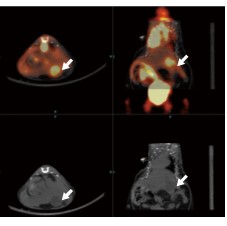

案例分析 5:肝原位癌

图5:上方是肝原位癌细胞摄取18F-FDG的微PET成像。下方是肝原位癌的CT扫描图像,白色箭头所指为肿瘤。